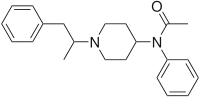

Anilidopiperidines